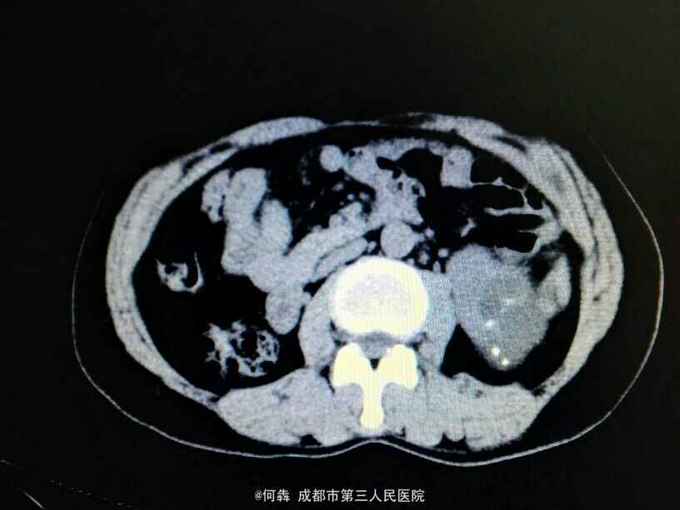

左肾区轻叩痛。尿常规:白细胞72个/ul。CT见图片。左侧GFR42.27,右侧GFR14.46。

左肾盂输尿管交界处结石 左肾重度积水,左肾结石,右肾萎缩,尿路感染。